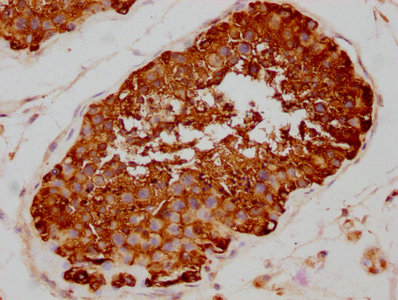

IHC image of CSB-RA011087A0HU diluted at 1:80 and staining in paraffin-embedded human testis tissue performed on a Leica BondTM system. After dewaxing and hydration, antigen retrieval was mediated by high pressure in a citrate buffer (pH 6.0). Section was blocked with 10% normal goat serum 30min at RT. Then primary antibody (1% BSA) was incubated at 4℃ overnight. The primary is detected by a biotinylated secondary antibody and visualized using an HRP conjugated SP system.